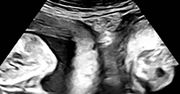

narodziny